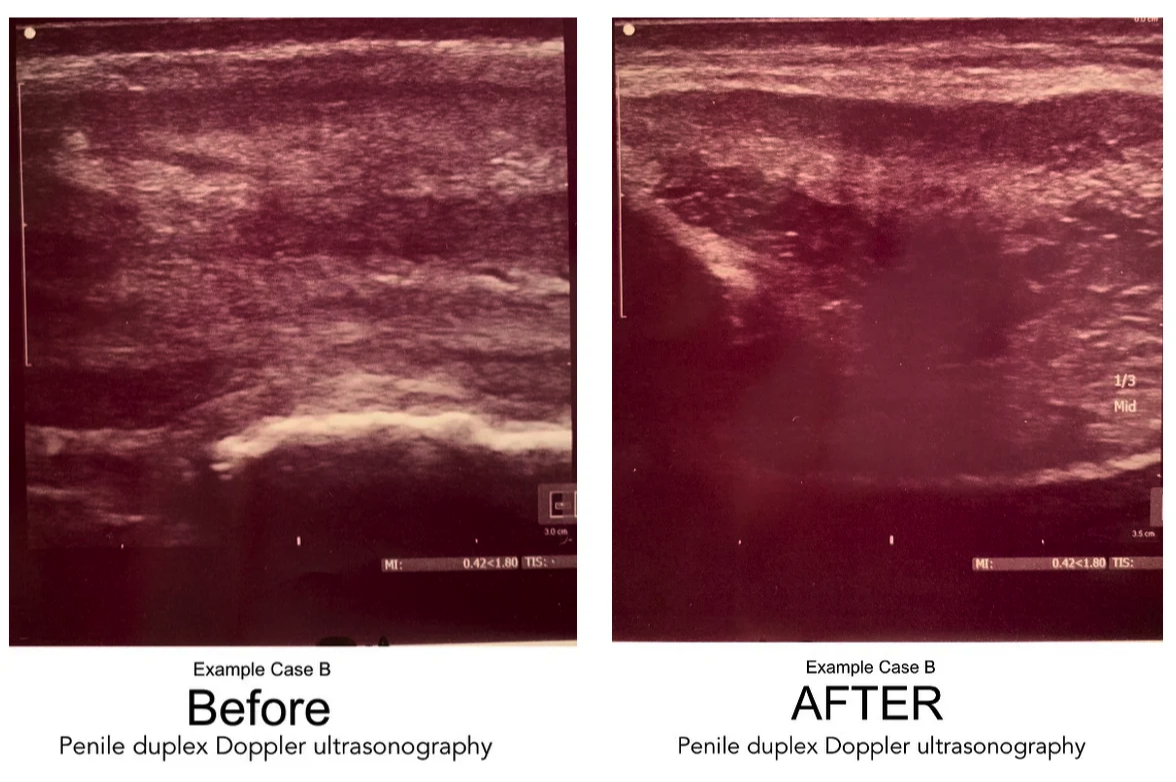

Highlights: Calcified Plaque Before & After Sonogram Images

Following is a set of four "before and after" duplex sonogram images of Peyronie's patients with calcified plaques